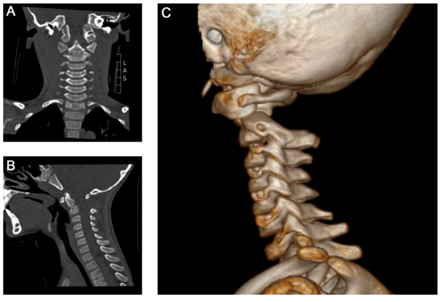

The patient was transferred to the operating room for closed reduction and internal fixation with two tension wires and a bone allograft according to the Brook’s procedure. The atlas was reduced during surgery by manual hyperextension of the head, also tilting up the ventrally deviated odontoid process. Fluoroscopy showed realignment of the odontoid process and anatomic reduction of the atlanto-axial joint. A bone-allograft from the pelvis was interponed and the intact laminae of atlas and axis were fixed by two tension wire loops. Control computed tomography before weaning showed anatomic reduction of both, the odontoid fracture and the C1-C2-dislocation (Figure 3).

Figure 3 Postoperative computed tomography with Brook’s tension wiring. A) Sagittal reonstruction showing realignment of the odontoid process and narrowed C1-C2 interspinous distance. B) Coronal view with intact facet joint alignment and central odontoid process. C) 3D-reconstruction with two paramedian C1-C2 tension wires and a 8-mm drain.